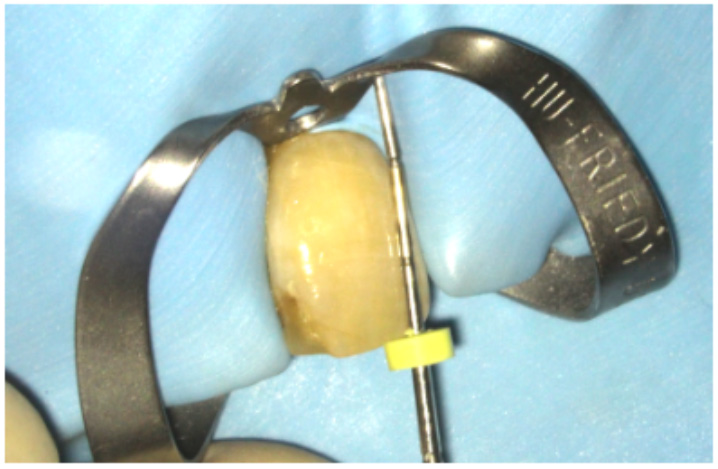

Preparation of the pulp space (Figure 7)

- Root canal retreatment (if required)

- Rubber dam isolation

- Removal of the access cavity restoration. Refine the shape of the access cavity to ensure the pulp horns are clean

- Removal of the coronal gutta percha to 3-4mm below the level of the cemento-enamel junction (CEJ) or gingivo-epithelial attachment. A heated plugger, gates-glidden or thin gooseneck burs are useful for cutting back the GP. A periodontal probe or Machtou plugger can be used to check the depth is sufficient

- Clean the cavity to remove any remnants of debris and sealer. An ultrasonic scaler is useful for this

- Place a 2-3mm barrier (subseal) over the GP. This will prevent bacteria or hydrogen peroxide from penetrating the root filling. Various materials have been suggested for this including IRM, GIC and composite. I prefer IRM because it is easy to handle. It also has a white colour and can be easily removed from the dentine walls. GIC or composite (especially the bonding agent) can sometimes remain on the canal wall and prevent the bleaching agent from penetrating the dentinal tubules

- Re-clean the dentine walls using an ultrasonic scaler

The best time to carry it out non-vital tooth whitening is immediately following endodontic treatment. This is because there is no permanent restorative material in the access cavity that needs removing.